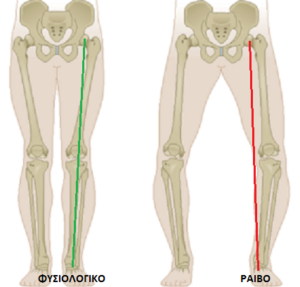

Σε κάποιες αρθρίτιδες, ιδίως μάλιστα αν η επιγονατίδα έχει σοβαρή φθορά, καθίσταται σχεδόν αδύνατη. Καθώς η φθορά προχωρά, ο πόνος είναι όλο και πιο συχνός και έντονος. Ο άξονας του γόνατος αλλάζει, γιατί συνήθως η διάβρωση είναι πιο μεγάλη από τη μία πλευρά. Αυτό συνήθως γίνεται στην έσω πλευρά και το γόνατο εμφανίζει μια «ραιβή» εικόνα. (εικόνα 6 ).